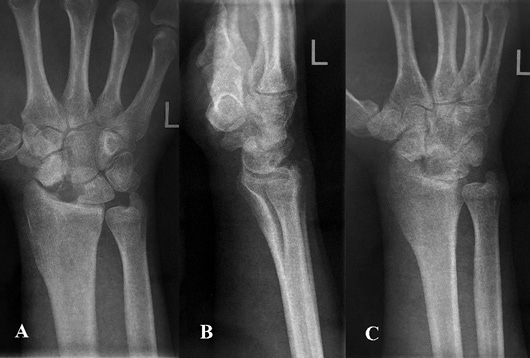

Pacientas pakartotinai klinikoje apsilankė praėjus 6 mėn. po rekonstrukcinės operacijos. Jis buvo patenkintas klinikiniais operacijos rezultatais, nes be apribojimų galėjo grįžti prie kasdienių veiklų ir darbo. Atlikus plaštakos goniometriją (žr. 3 pav.), įvertinti klinikiniai rezultatai, pasitelkiant modifikuotą Greeno ir O’Brieno riešo funkcijos balą ir Quick Disabilities of the Arm, Shoulder and Hand (QuickDASH) klausimyną, taip pat atliktos riešo rentgenogramos. Modifikuotas Greeno ir O’Brieno riešo funkcijos balas siekė 95. Balo įvertis, palyginti su pradiniu, prieš rekonstrukcinę operaciją apskaičiuotu įverčiu, padidėjo daugiau negu 20 balų, visų vertintų kategorijų, išskyrus riešo judesių amplitudę, įvertinimai buvo aukščiausi, atitinkantys sveikosios plaštakos rodiklius. Įvertinus Quick Disabilities of the Arm, Shoulder and Hand (QuickDASH) klausimyną, apskaičiuota skaitinė išraiška siekė 4,55 balų, t. y., palyginti su pradiniu įverčiu, sumažėjo 9,09 balų. Paciento atsakymuose fiksuoti minimalūs kasdienės veiklos ribojimai. Taip pat atliktos kairiojo riešo trijų krypčių rentgenogramos (žr. 4 pav.).

triju.jpg

4 pav. Kairiojo riešo trijų krypčių rentgenogramos, praėjus 6 mėn. po operacijos: priekinė rentgenograma (A), šoninė rentgenograma (B), įstrižinė rentgenograma (C)